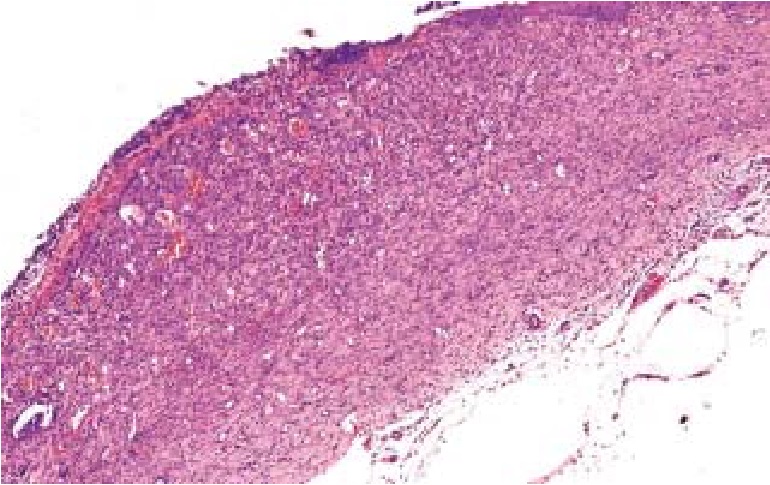

При гистологическом исследовании биоптатов ран установлено, что у животных контрольной группы к 14-м суткам в области раны определяется крупный раневой дефект со значительным количеством гнойного экссудата на поверхности. Субэпителиально визуализируется волокнистая ткань дермы без деления на сосочковый и сетчатый слои, с массивными кровоизлияниями и очаговыми лимфогистиоцитарными инфильтратами, примесью нейтрофильных лейкоцитов, что отражает продолжающиеся процессы воспаления и полное отсутствие переключения репаративных процессов на фазу реэпителизации (рис. 2) [10].

Рис. 2. Гистологический срез биоптата раны в зоне ожога кожи III степени после ранней некрэктомии, без лечения, 14-е сутки наблюдения. Субэпителиально определяется волокнистая ткань дермы без деления на сосочковый и сетчатый слои с массивными кровоизлияниями, очаговыми инфильтратами и гнойным отделяемым. Окраска гематоксилин-эозином, ув. ×200